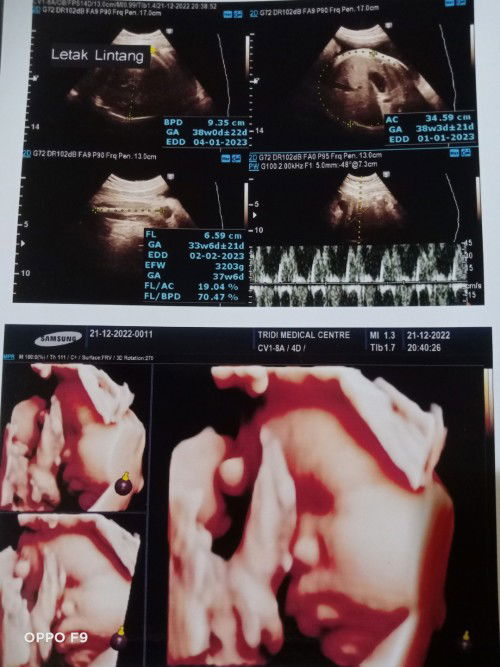

Bun ini hasil USG tgl 21 des,hpl nya jd maju Krn BBJ gede,hpl awal 15 Jan(37w klo dihitung HR ni)

Dr udh ksh surat rujukan operasi tgl 28 ini.yg berarti klo menurut hpl awal lahir di 37w3d,,tp klo nurut usg terakhir ini lahir di 38an w,,apa udh cukup matang ya tuk dilahirkan diusia segitu..saya ada riwayat mioma jg,dan wkt tgl 21 cek itu bayi posisi lintang dan air ketuban sedikit keruh.jd sedikit was was jg si ..tp dr nya blg udh siap dan matang kok tuk dilahirkan??apa bener ya Bun? soalnya anak pertama saya lahir lewat dari hpl 40 an Minggu LBH..